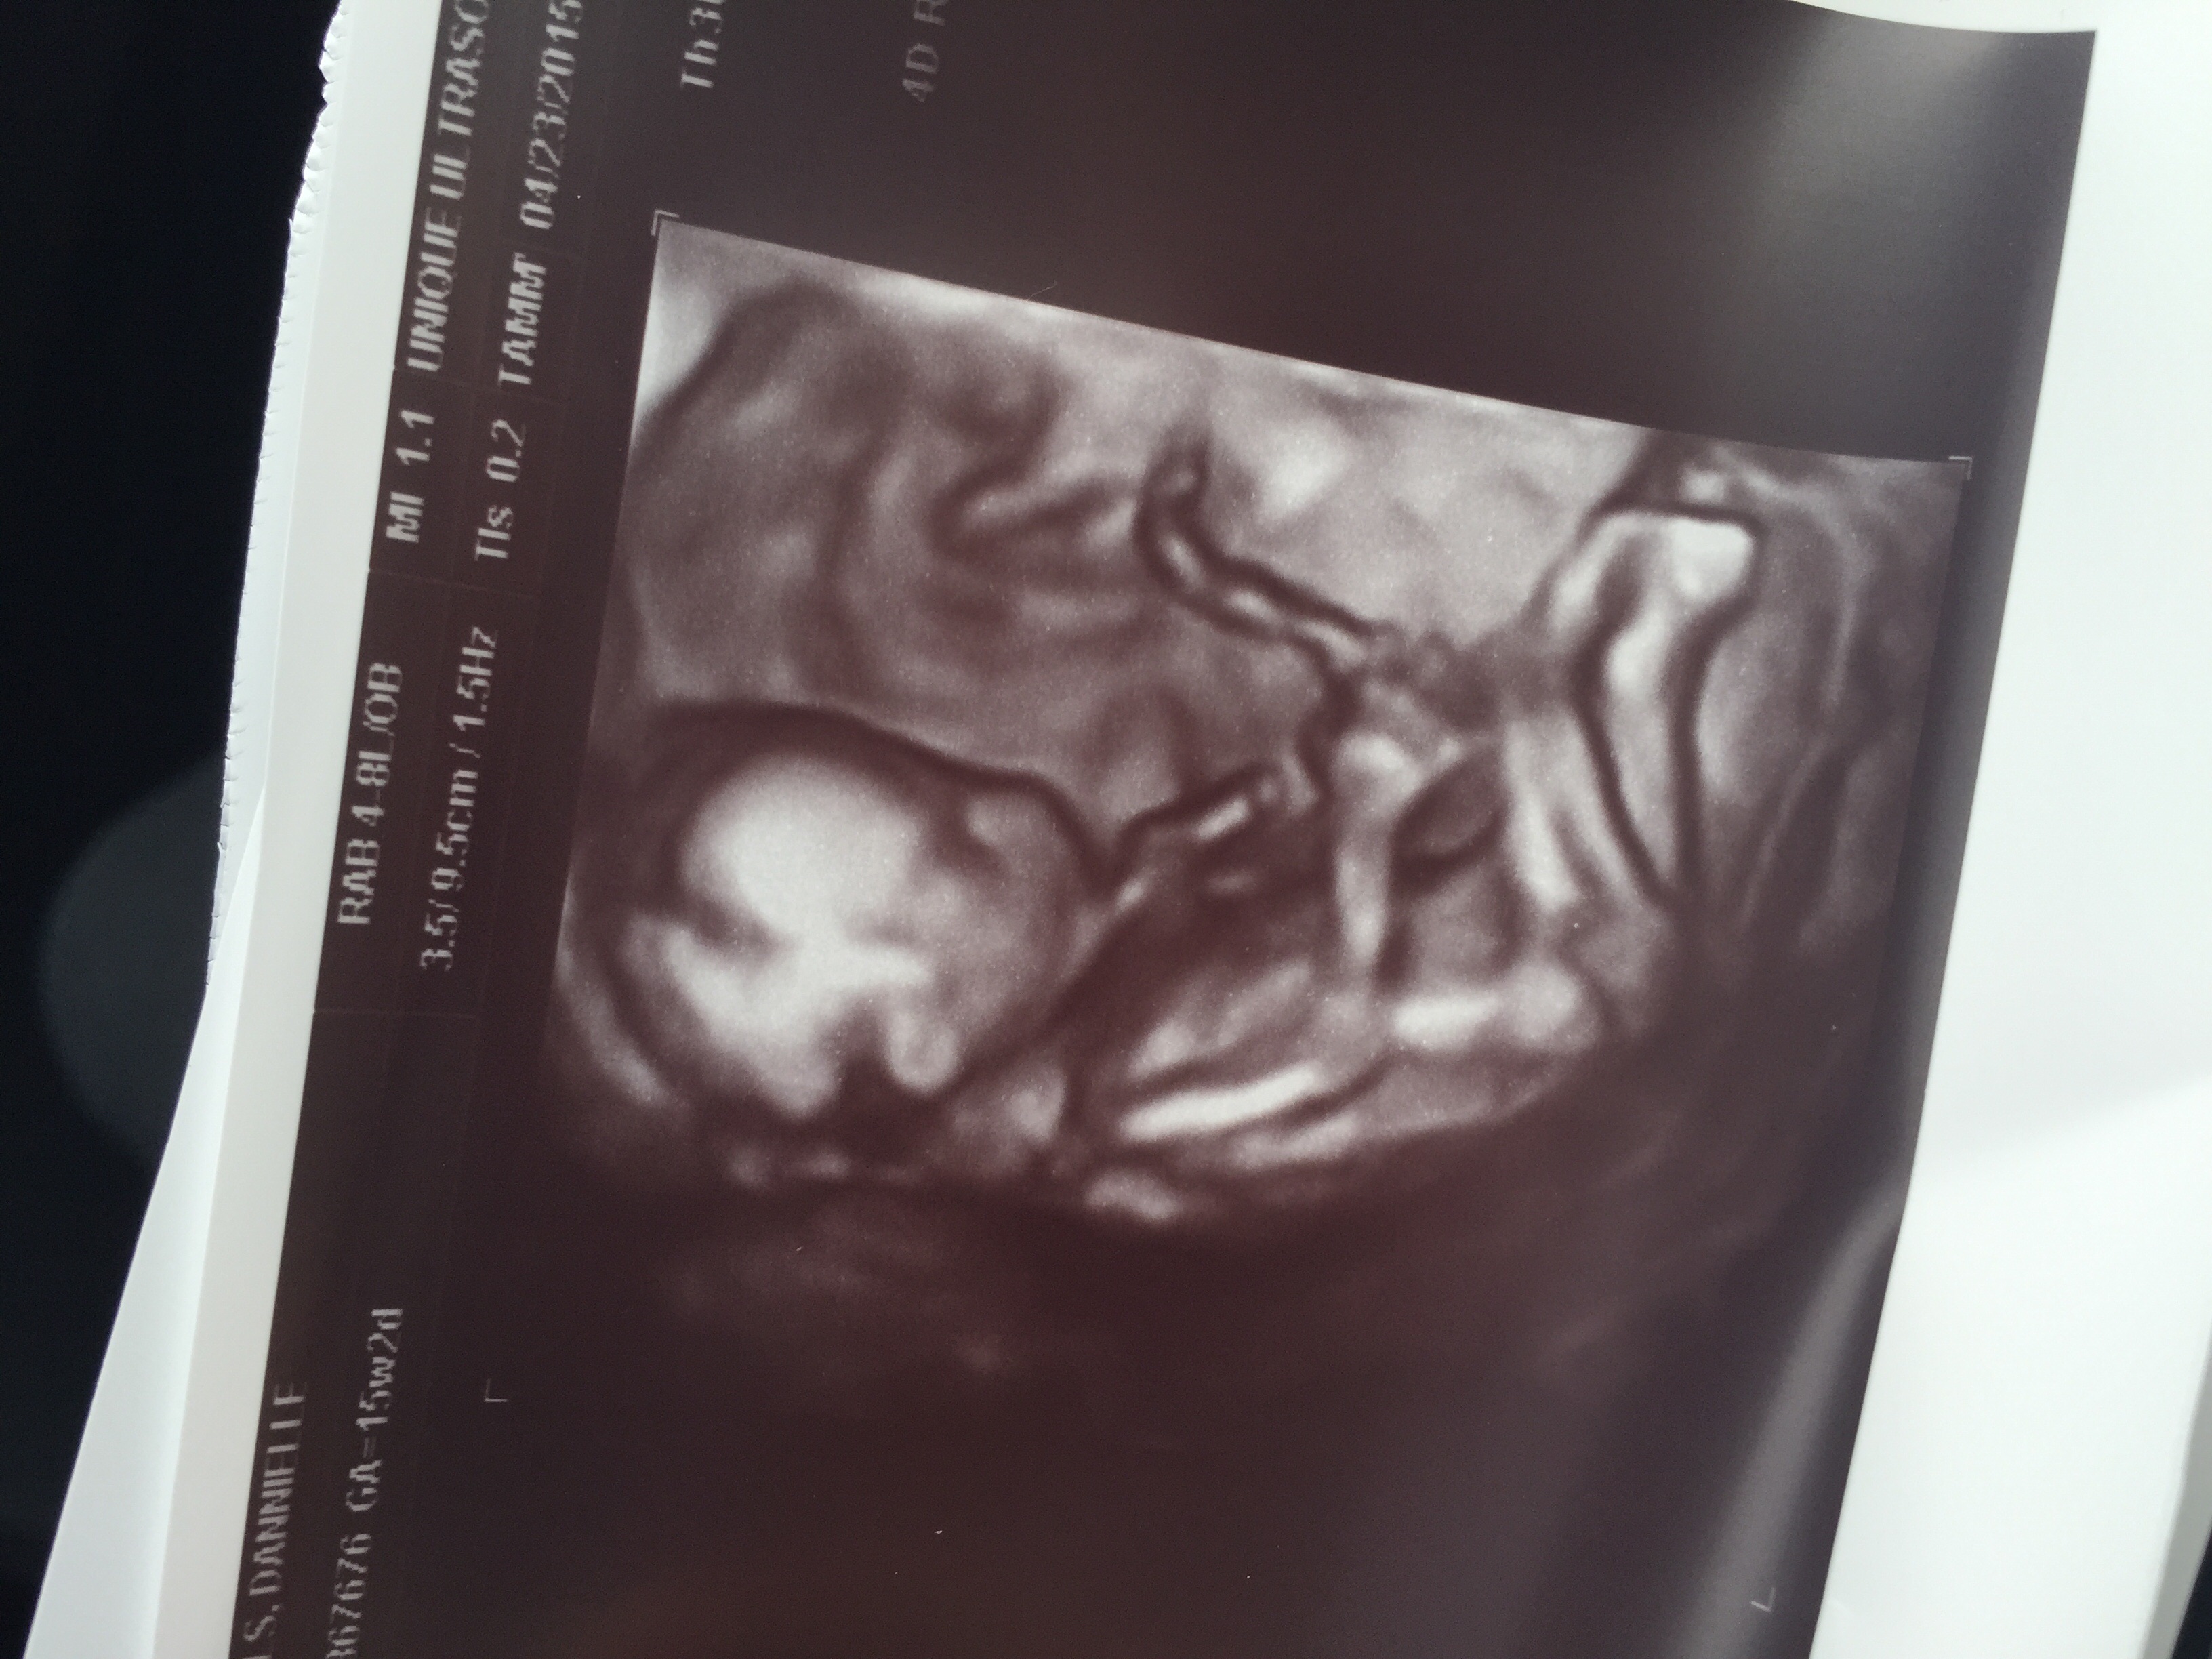

• I had one today at 15 weeks 1 day and it was such an amazing experience! It's a BOY! It took about 10 minutes for her to find his parts but after wiggling me around and having me cough it was clear we are having a boy! I definitely recommend going to one it was a great experience !!

Here is a photo from our ultrasound :